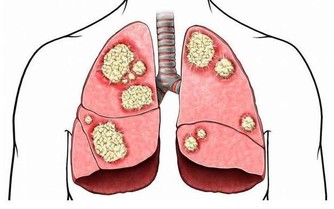

一旦反復出現這些症狀,不但會導致整體的免疫功能受到影響,還會影響到心臟的正常供血,患有心梗或者是冠心病等一系列心血管疾病的概率會比較高。所以在進入夏季時,一定要做好心臟的養護工作。那麼,在夏季時到底該如何養護心臟呢?

在進入夏季時,尤其是對於患有一些高血壓、高脂血症的人群來講,一定要做好睡眠方面的調整,一旦睡眠不足,就會導致心跳速度改變,血管也會異常痙攣,從而影響到心臟的供血,發生心肌缺血、缺氧的概率會特別高。

而一旦出現暴躁、易怒、焦慮、緊張情緒,會導致體內的各種激素異常分泌,從而影響到心跳節律,出現心律失常以及患上冠心病甚至是心梗的概率都會提高。

過度貪涼,是導致夏季突發心梗的主要誘因之一。因為在過熱環境當中,血管會處於擴張狀態,而一旦進入空調室內會使血管受到強烈刺激而異常收縮,就會影響到心臟的供血,發生心梗的概率自然會增高。